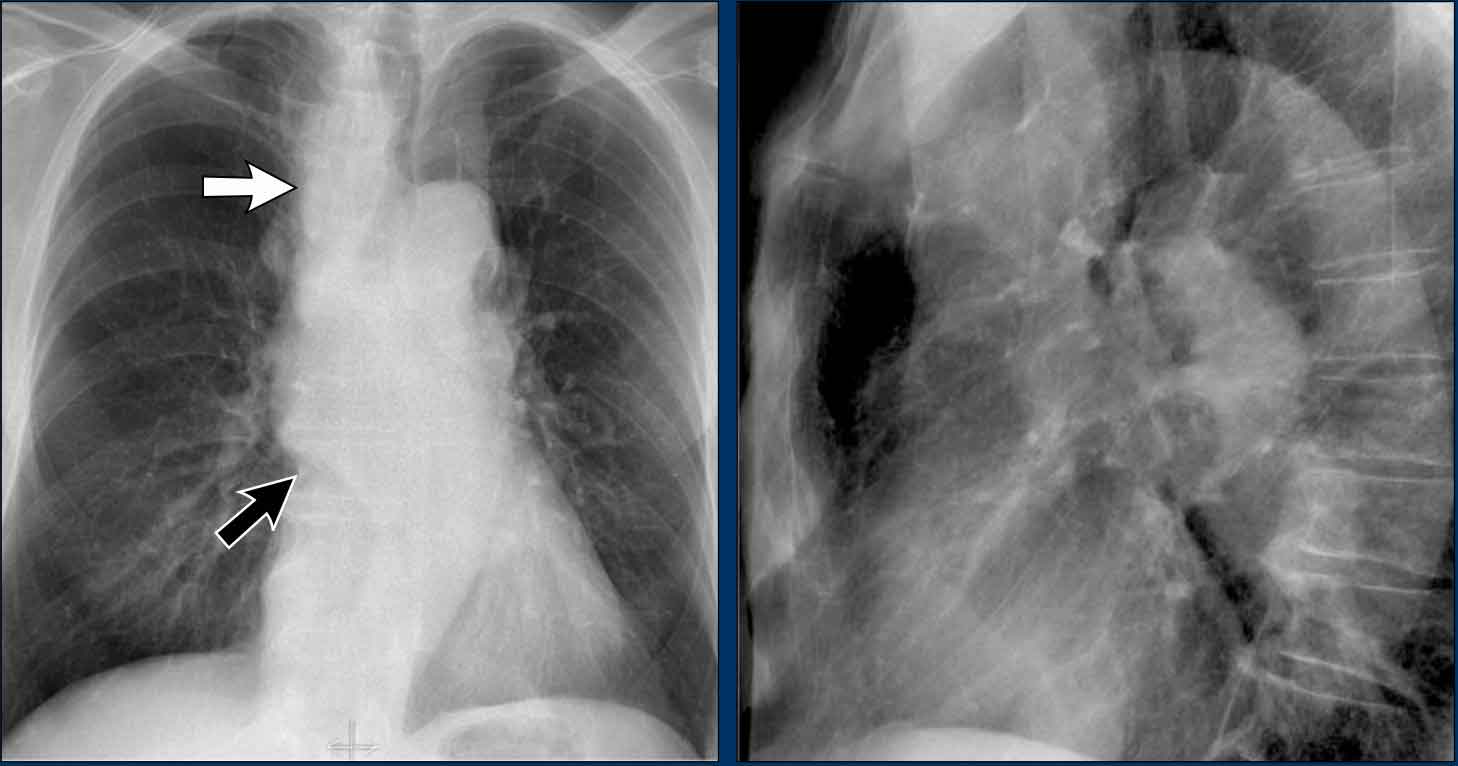

Displacement of the Azygoesophageal Line (2) – Subcarinal Lymphadenopathy

A common cause of displacement of the azygoesophageal line is subcarinal lymphadenopathy (station 7).

On the chest X-ray, note superior displacement of the azygoesophageal line just below the carina, consistent with enlarged subcarinal lymph nodes (black arrow).

Additional right paratracheal lymphadenopathy is seen, displacing the right paratracheal stripe (white arrow) and deviating the trachea to the left.

Continue with PET-CT...

PET Imaging

- PET-CT demonstrates extensive hypermetabolic lymphadenopathy in the mediastinum and neck, which is more conspicuous than on chest radiography.

- Cervical lymph nodes are involved—an important finding as they are accessible for biopsy.

Continue with images of CT and ultrasound...

CT Imaging

- Contrast-enhanced CT shows bulky subcarinal lymphadenopathy displacing the azygoesophageal recess and compressing the left atrium.

- Biopsy of a cervical node confirmed small cell lung carcinoma.